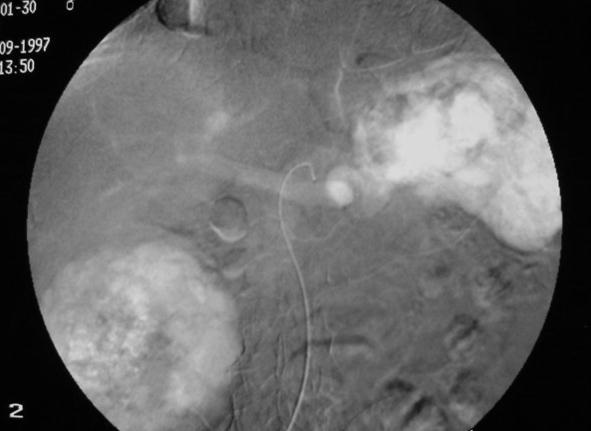

碘化油的量取决于肿瘤的大小和血管分布,导管置入部位,和肝功能受损情况。一般剂量为3至10毫升。在靶动脉内放置的导管内注射2%的利多卡因5ml后再进行化学栓塞注射。这样可以避免在操作过程中或操作刚结束时肝脏内产生的剧烈疼痛。然后,抗肿瘤药物与碘化油的混合物被缓慢注入。最后,被剪成小块状的明胶海绵或海绵颗粒或PVA与造影剂和少量的抗肿瘤药物的混合物注入肝动脉。如果存在肝外侧支动脉,则在此动脉中也应放置导管,进行化学栓塞。如果存在显著的动-门脉短路,则在注入碘化油乳剂前,应首先注入少量明胶海绵以阻断血流。动-肝静脉短路也应该被同样处理,但在注入碘化油之前寻找是否有到体循环的短路是最重要的,避免肝动脉栓塞后的肺栓塞。 注入碘化油乳剂之后,应进行数字减影血管造影(DSA),从而确定肿瘤染色是否已经消失。术后定期应拍摄腹部X线片,以确定碘化油是否持续沉积。

碘油乳剂的栓塞终点:新生血管的阻塞,意味着应避免肿瘤滋养动脉出现血流停滞。对于常规TACE来说栓塞时知道门静脉分支可见时是最理想的。而对于DEB-TACE,我们需要血流载运微球,所以心脏两、三跳之后造影剂消失。

最理想的是栓塞时门静脉分支可以看见